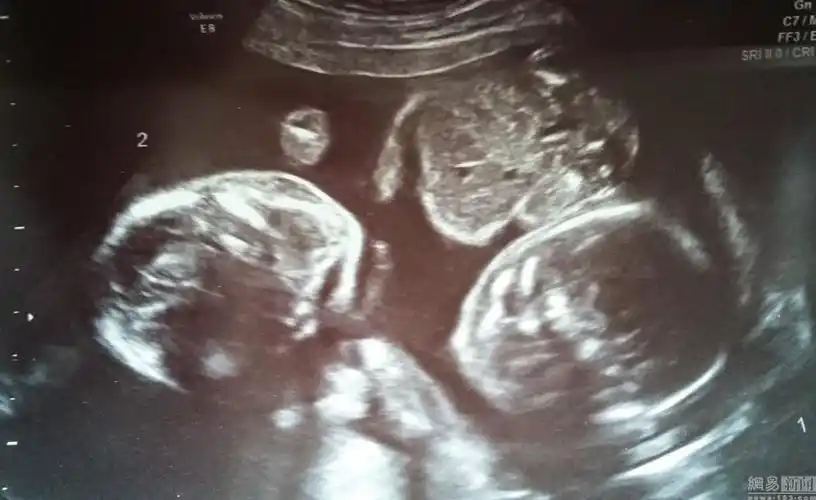

双胞胎共享羊膜囊靠手挽手奇迹存活